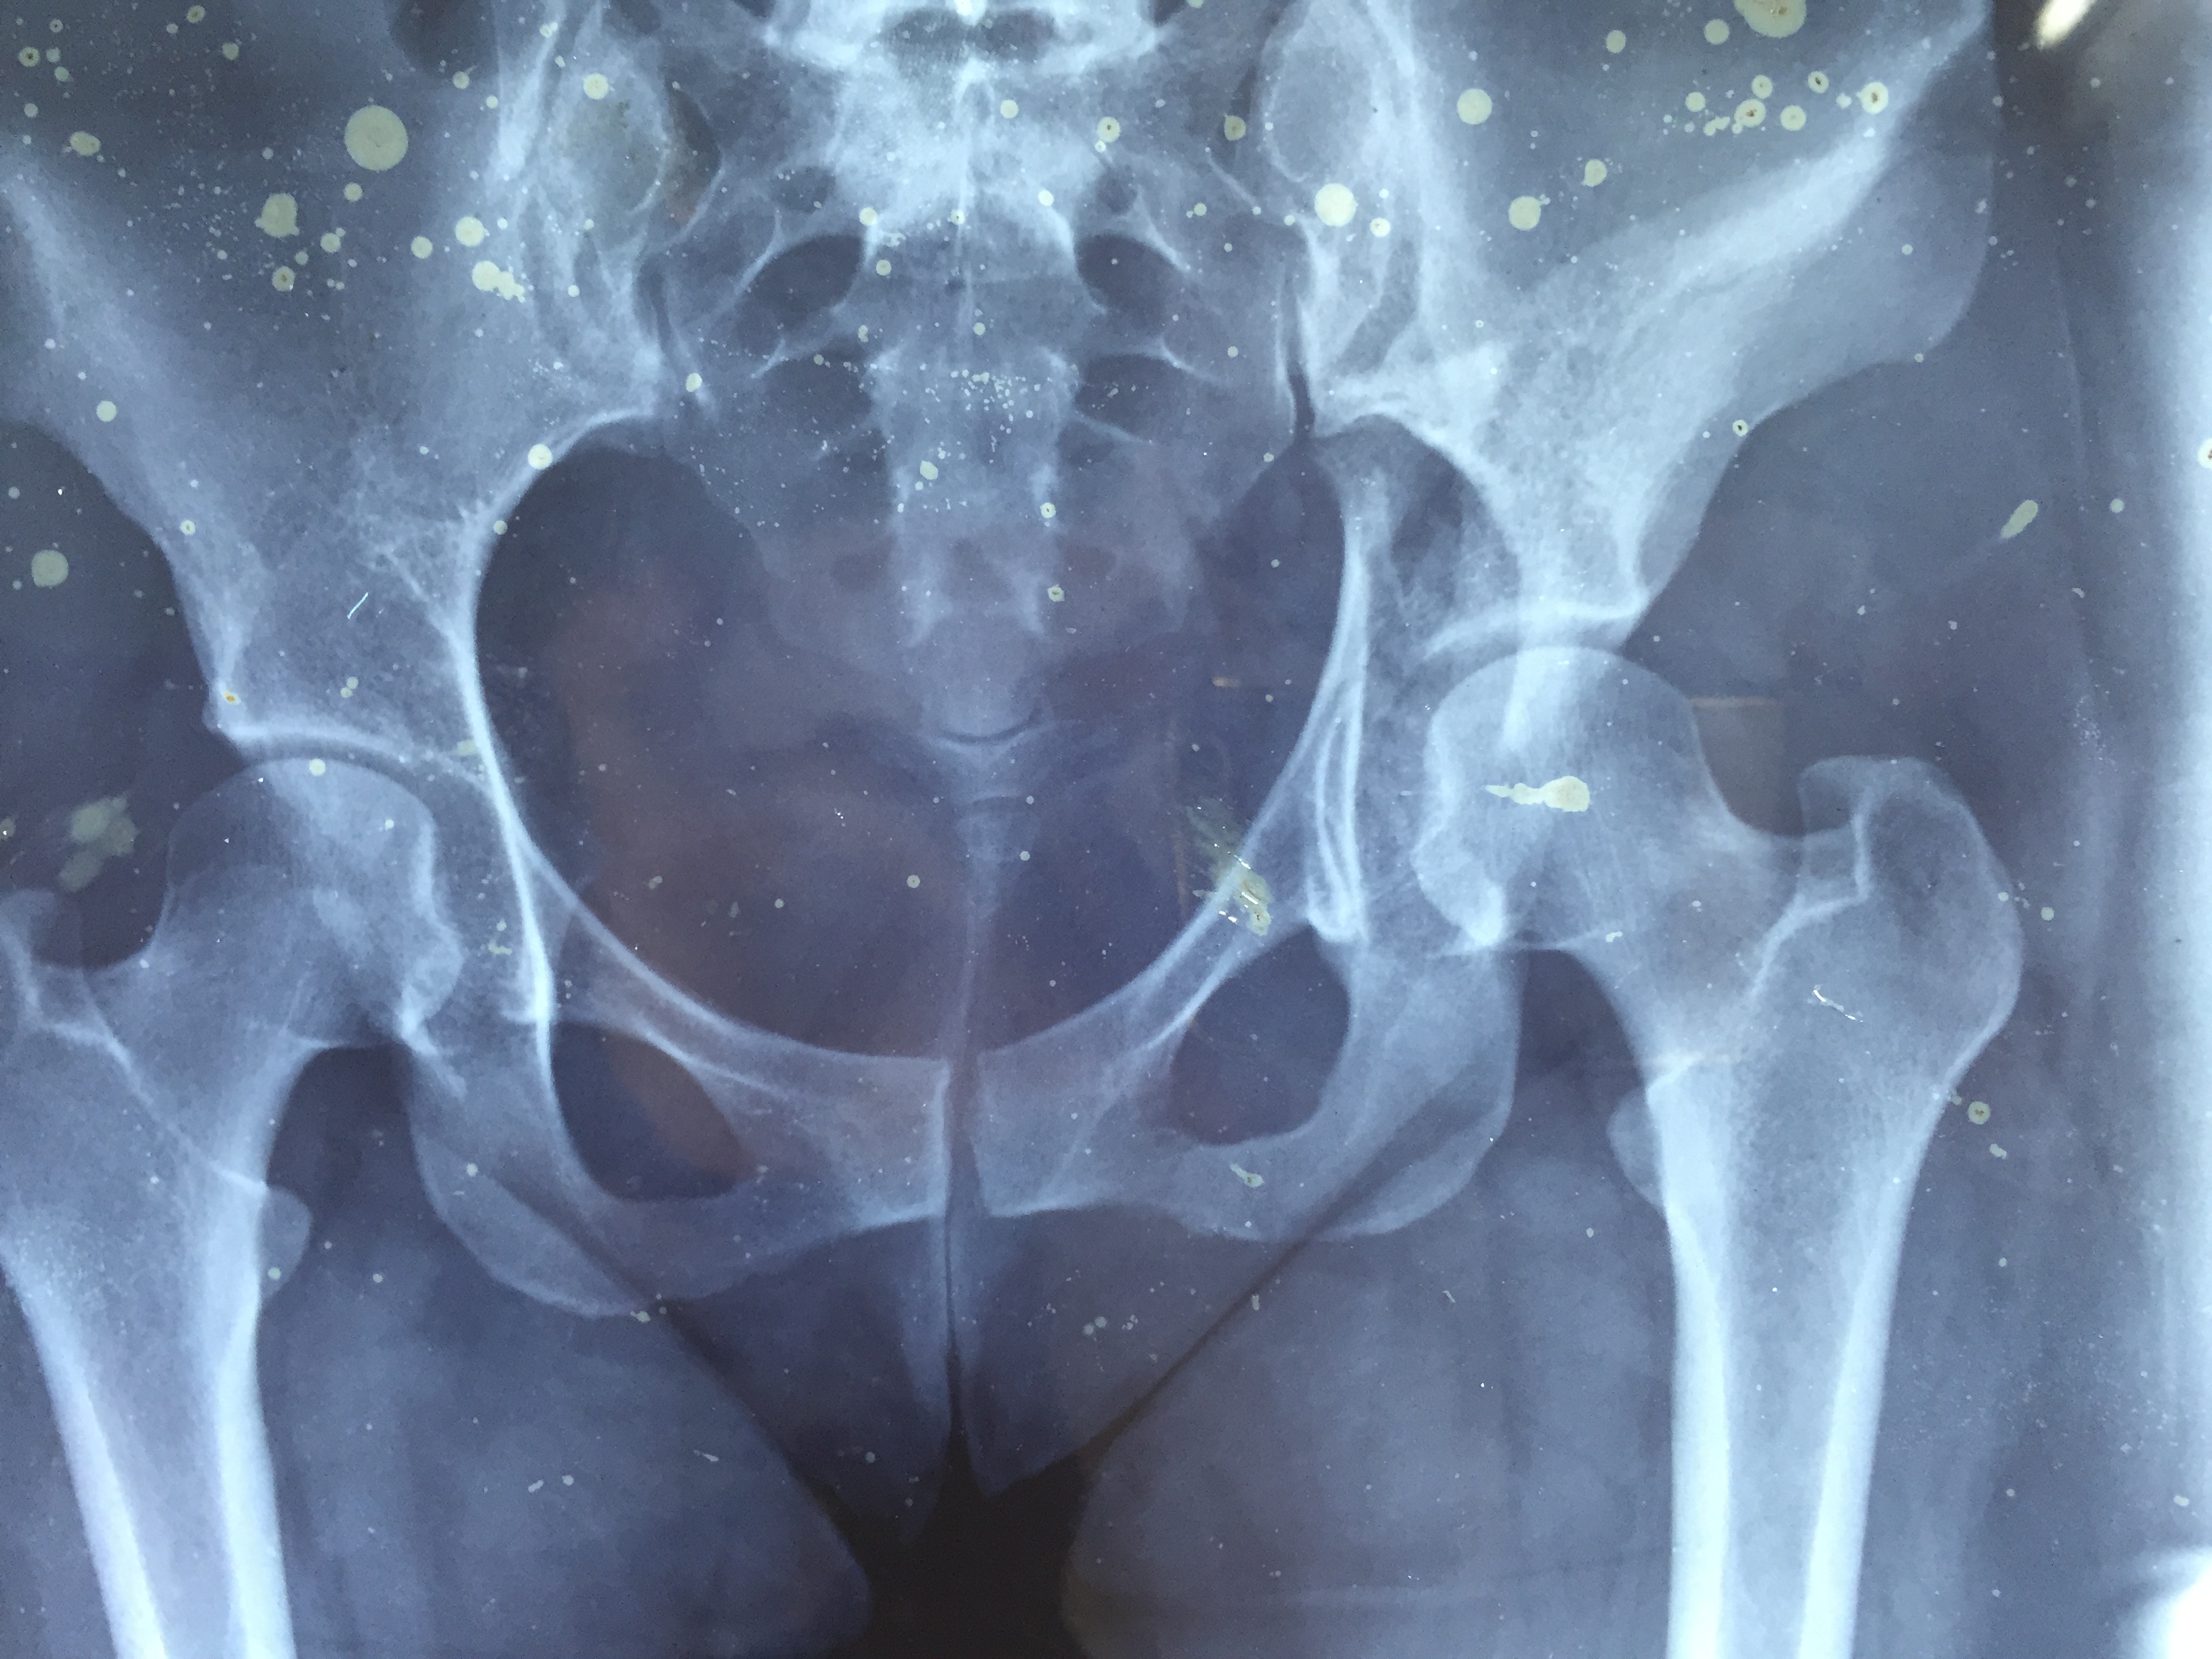

How is a fracture Diagnosed?

In order to determine the cause of a fracture, a doctor will inquire about the circumstances involved. A physical examination will then be performed to determine the cause. They will often order an X-ray and, in some cases, an MRI or CT scan in order to fully assess the fracture.